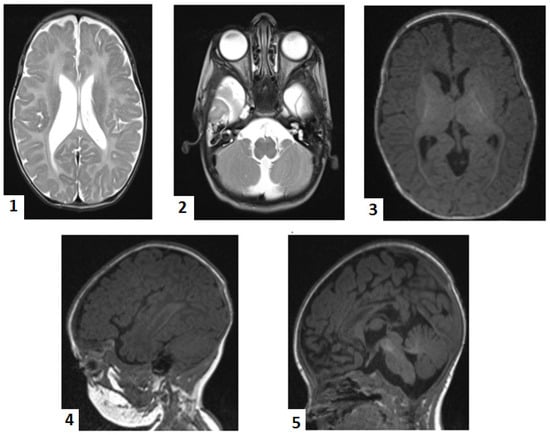

At 2 months, brain magnetic resonance imaging (MRI) showed bilateral perisylvian polymicrogyria, delayed partial myelination of the posterior limb of the internal capsule, cerebellar atrophy (central lobule and culmen) with secondary mega cisterna magna, callosal dysgenesis, and bilateral temporal subarachnoid cysts (Figure 1). These findings led us to suspect a rare neurodegenerative disorder. We then performed a genetic test on the patient’s buccal swab using whole-exome sequencing (Blueprint Genetics Whole Exome Plus Test version 2, Espoo, Finland, 9 February 2018). The results showed that the patient had two homozygous mutations: HSD17B4 c.788del.p(Pro263GInfs*2) (NM_000141.4) and SUOX c.913G>A, p.(Ala305Thr)(NM_000456.3). Upon searching in genetic databases (ClinVar, gnomAD, HGMD), it was found that the HSD17B4 variant was previously reported once as pathogenic in ClinVar [10]. However, the SUOX variant, although previously reported once in the heterozygous variant in gnomAD, was predicted as deleterious by some in silico tools, including PolyPhen and MUTTASTER. Technical details on WES workflow are presented in the Supplementary Materials. We offered genetic counseling to the parents and stopped further biochemical confirmation of the D-BPD. This decision was taken as the extended metabolic screening and all of the genetic tests performed up to this moment were supported by a non-governmental charity organization. Given the lethal outcome, the parents refused other investigations.

Figure 1. Magnetic resonance imaging: 1. enlarged ventricles; 2. bilateral temporal subarachnoid cyst, mega cisterna magna; 3. delayed partial myelination of the posterior limb of the internal capsule; 4. bilateral perisylvian polymicrogyria; 5. cerebellar atrophy (central lobule, culmen), dysgenesis of the corpus callosum.

We could rule out Pompe disease and SMA by accessing free tests. However, not even routine genetic testing is not covered by the state Health Insurance House in Romania. As the infant’s seizures worsened and became more frequent and difficult to control, a non-governmental charity organization helped to conduct a genetic test for epilepsies, which also came back negative. Repeated cranial ultrasounds during the neonatal period showed non-specific aspects, prompting an MRI at two months. The MRI results suggested rare neurodegenerative disorders. The MRI scan was extremely helpful, providing crucial information, as there are reports of D-BPD cases with normal imaging aspects [3,20,35]. Germinolytic cysts are relatively common neuroimaging findings in D-BPD [4,18,35].

Whole-exome sequencing revealed that our patient was homozygous for the variant HSD17B4 c.788del, p.(Pro263GInfs*2). The variant is absent in gnomAD but is reported in ClinVar. The defect is located on exon 12 and consists of the deletion of a base pair, generating a frameshift that prematurely stops codon2 amino acids downstream. The variant predicts either a truncation of the encoded protein or the absence of the protein, a common mechanism for disease [38]. Consequently, the patient was classified as having type I D-BPD, which matches its severe phenotype. Ferdinandusse et al. [9,11] proposed a genotype–phenotype correlation, as the depicted residual activity of D-BP was associated with less severe phenotypes in their cohort, and the mutation effect on the protein structure may predict the phenotype. This homozygous variant was previously described in 2006 in the cohort of Ferdinandusse et al. [9] and classified as pathogenic and associated with D-BPD (PMID 16385454). An unpublished observation in ClinVar reported an association of the same homozygous mutation in a patient with polymicrogyria, partial callosal agenesis, congenital hypotonia, epilepsy, developmental delay, dysmorphic features, anemia, and abnormal eye movement [38]. Other laboratories also detected the variant in the context of clinical testing (variation ID 632859 in ClinVar) [38]. Similarly, congenital hypotonia, epileptic seizures, polymicrogyria, callosal dysgenesis, and severe psychomotor delays were found in our patient.